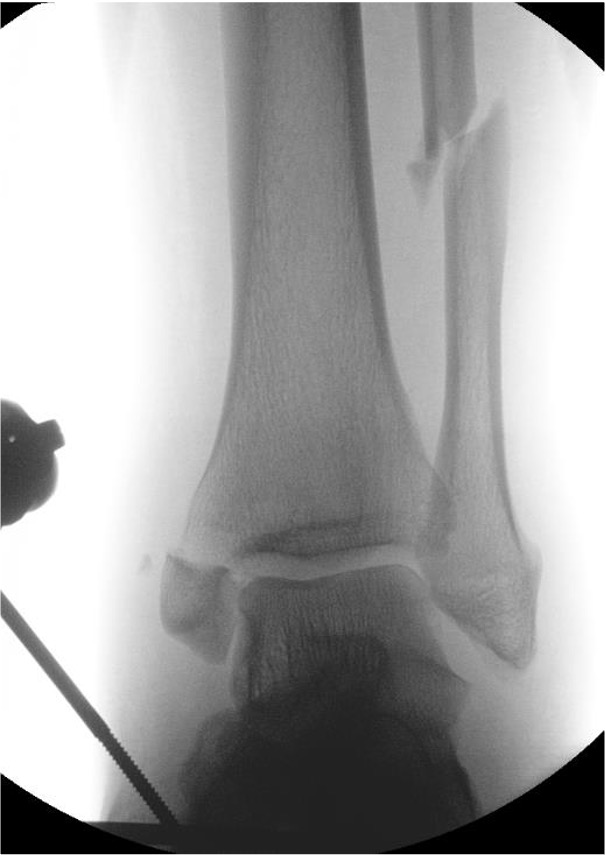

Lateral talar shift / increased medial clear space / deltoid ligament injury

Ankle Fracture Increased Medial Clear SpaceAnkle Fracture Increased Medial Clear Space 2Maisonnerve

Tibia / fibular overlap < 1mm / syndesmotic injury

Ankle Fracture Syndesmosis WidenedAnkle Diastasis